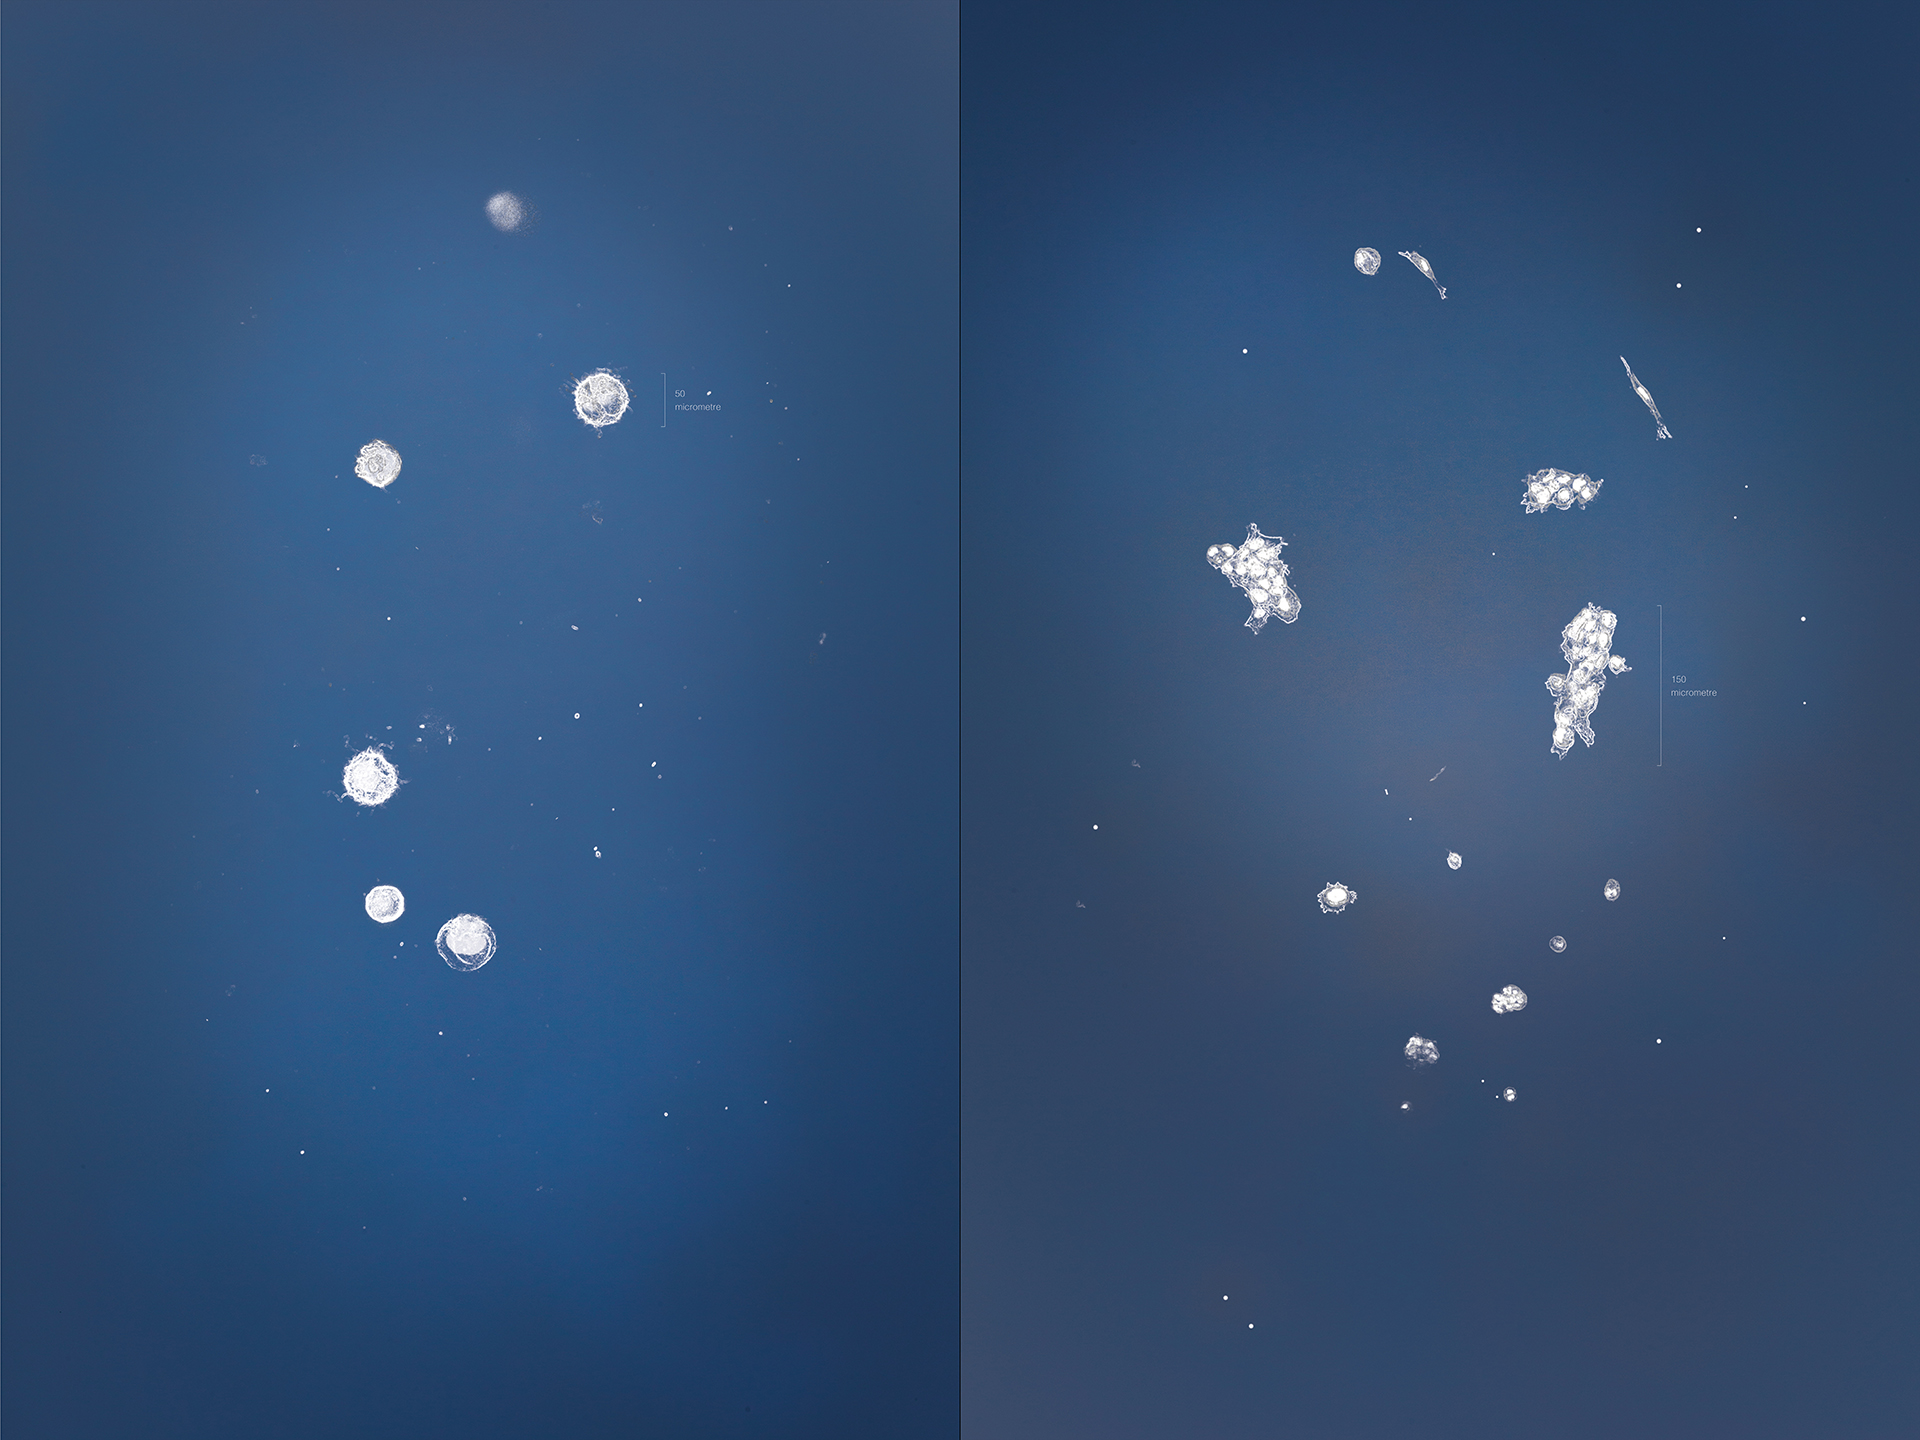

Many processes within the body are changed by the presence of cancer. These images show the response of microglia, immune defense cells in the brain, to cancer cells. When microglia encounter glioblastoma multiforme, one of the most aggressive brain cancers, they shift from a relaxed, elongated shape to a rounded, ready-for-combat conformation.

These images echo the work of Anna Atkins, a British botanist and photographer who used a contact printing technique called cyanotyping to capture the form of plants and algae. Emily Chen’s work similarly seeks to explore biological function, in this case the immune response to brain cancer, by capturing and comparing biological forms.